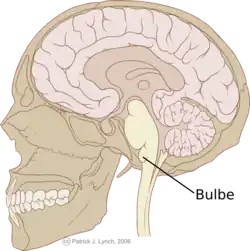

La moelle allongée (ou medulla oblongata, aussi appelée bulbe rachidien en ancienne nomenclature ou myélencéphale) est la partie inférieure du tronc cérébral (la plus caudale) chez les chordés. Elle prolonge en haut la moelle spinale et se situe en avant du cervelet dans la fosse postérieure du crâne. Elle est en continuité en haut avec le pont. Dans l'ancienne nomenclature, on remarque que le terme « rachidien » est un composé de « rachis », du grec ancien ῥάχις / rhákhis, « épine dorsale »[1] (élargi par analogie avec des mots de radical en -id-). Cette moelle allongée est percée d'un conduit permettant la circulation du liquide céphalorachidien, ce conduit étant en continuité avec le 4e ventricule en haut et le canal de l'épendyme en bas.